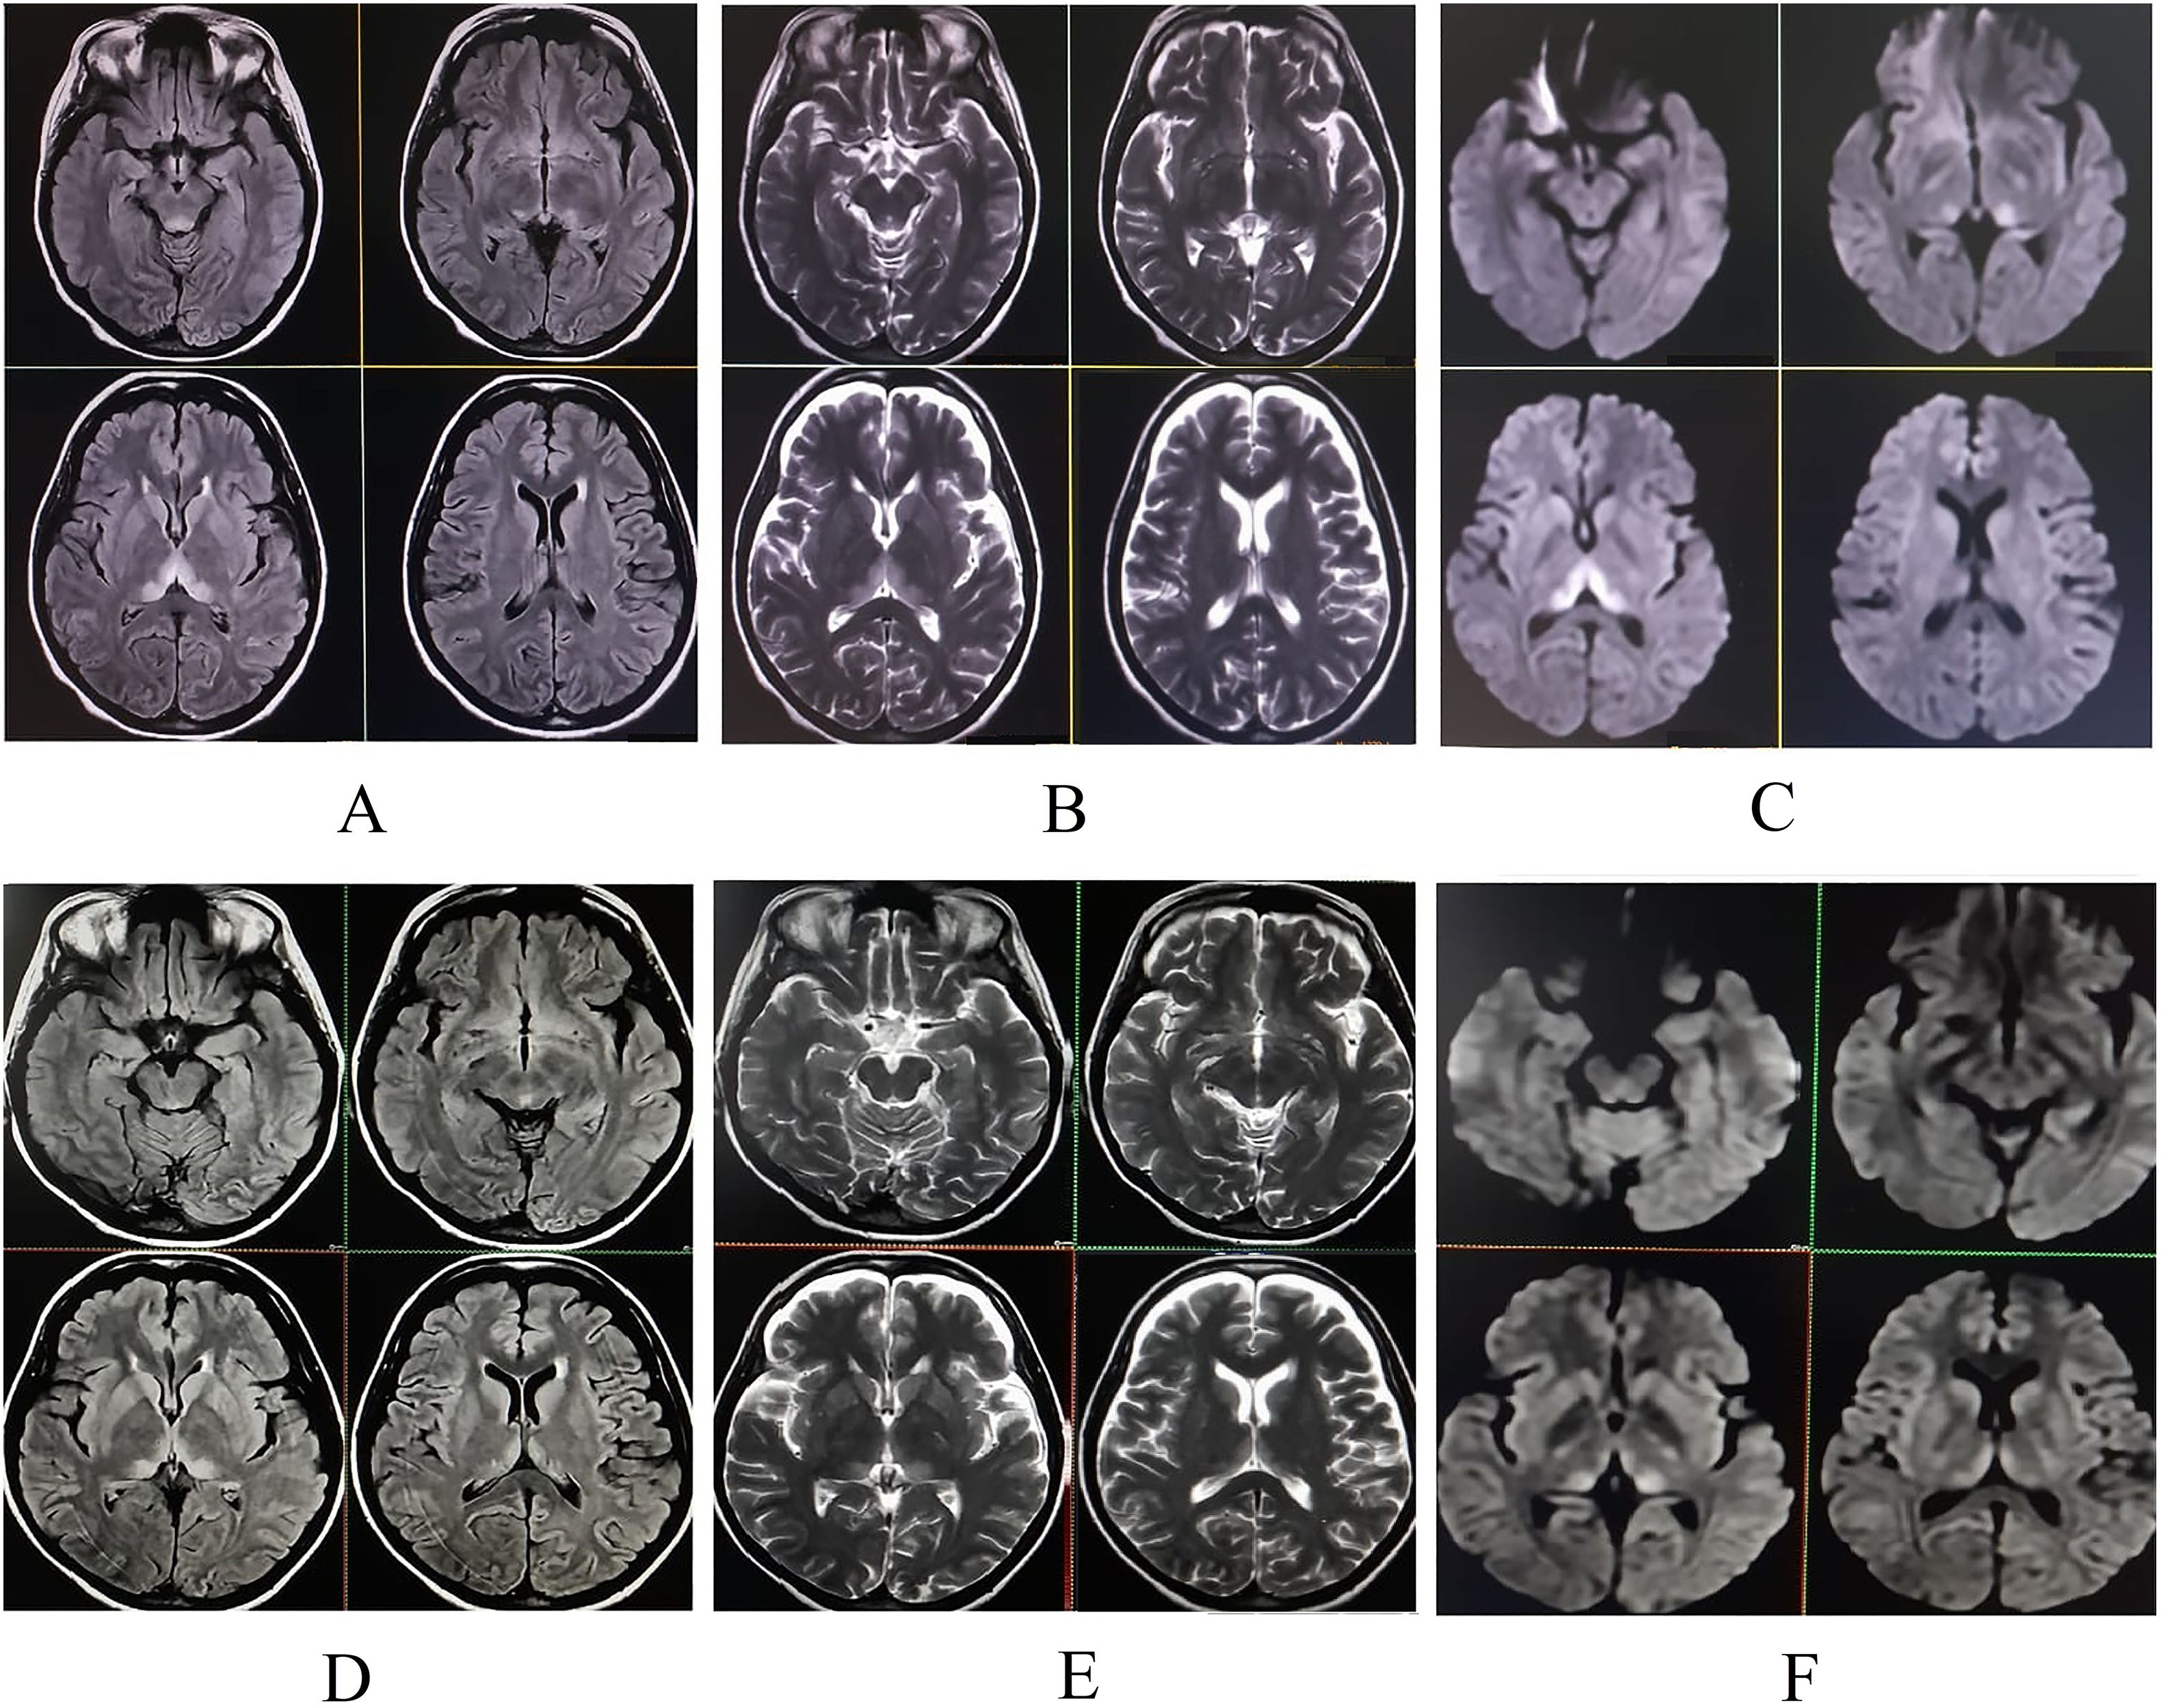

Neurodegeneration with brain iron accumulation: two decades of pediatric cases in a Portuguese Center

Background Neurodegeneration with brain iron accumulation (NBIA) comprises a group of rare and heterogeneous genetic disorders, in which early diagnosis can be challenging. Cases Retrospective review of clinical, neurophysiological, radiological, and molecular data from 18 […]